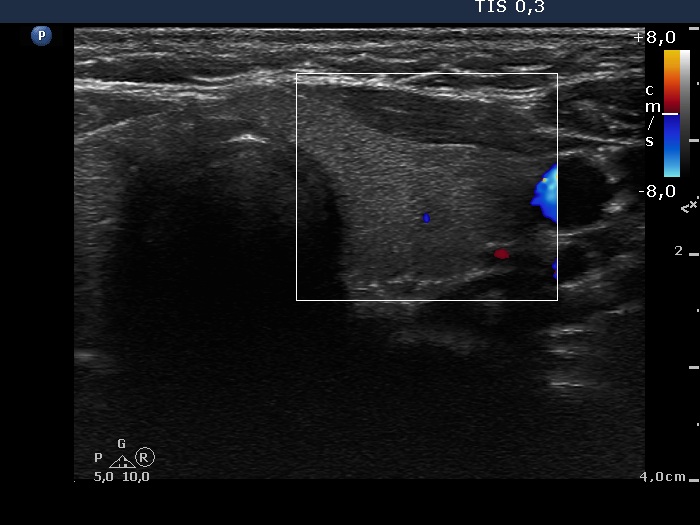

Halo sign and vascular pattern of nodules - case 738 (ultrasonographic picture 6)

Left lobe, transverse scan, color Doppler mode. The vascularization is scanty.